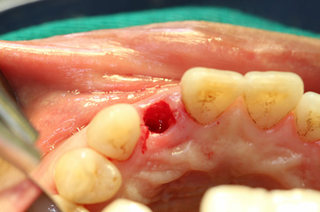

牙齿拔除之后

安装种植体